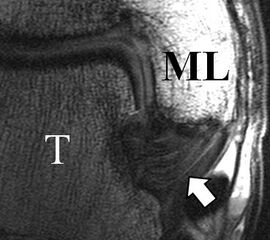

Physiologische Bandlücke (Pfeil)

Abbildung 9b

Zu Fehlinterpretationen eines intakten LFTA führt unter Umständen das unmittelbar kaudal des LFTA parallel verlaufende Ligamentum talocalcaneum laterale (Abb. 9 a). Dieses kann bei Verwendung von Schichtdicken um die 3 mm trotz Ruptur des LFTA durch Volumenteileffekte mit Anschnittsphänomenen einen intakten Bandverlauf vortäuschen.

Eine Ursache der falschen Diagnose einer LFTA-Ruptur ist die Fehlinterpretation der physiologische Bandlücke zwischen dem LFTA und der vorderen Syndesmose als traumatischer Banddefekt (Abb. 9 b).

Die Interpretation pathologischer Veränderungen sollte daher immer multiplanar unter Verwendung möglichst dünner Schichtdicken und hoher Ortsauflösungen erfolgen, um Fehldiagnosen zu vermeiden.